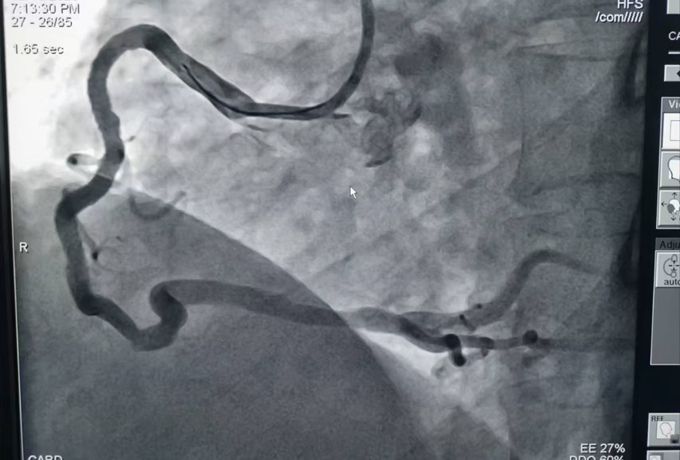

術(shù)前造影

為準(zhǔn)確判斷病情,建議立即行冠脈造影檢查。進(jìn)一步的冠脈造影結(jié)果證實了醫(yī)生的判斷,而檢查結(jié)果也著實讓人揪心:患者三支心臟主血管均存在嚴(yán)重彌漫性鈣化病變,且嚴(yán)重狹窄,尤其是其中兩根較為嚴(yán)重,最重狹窄為次全閉塞。